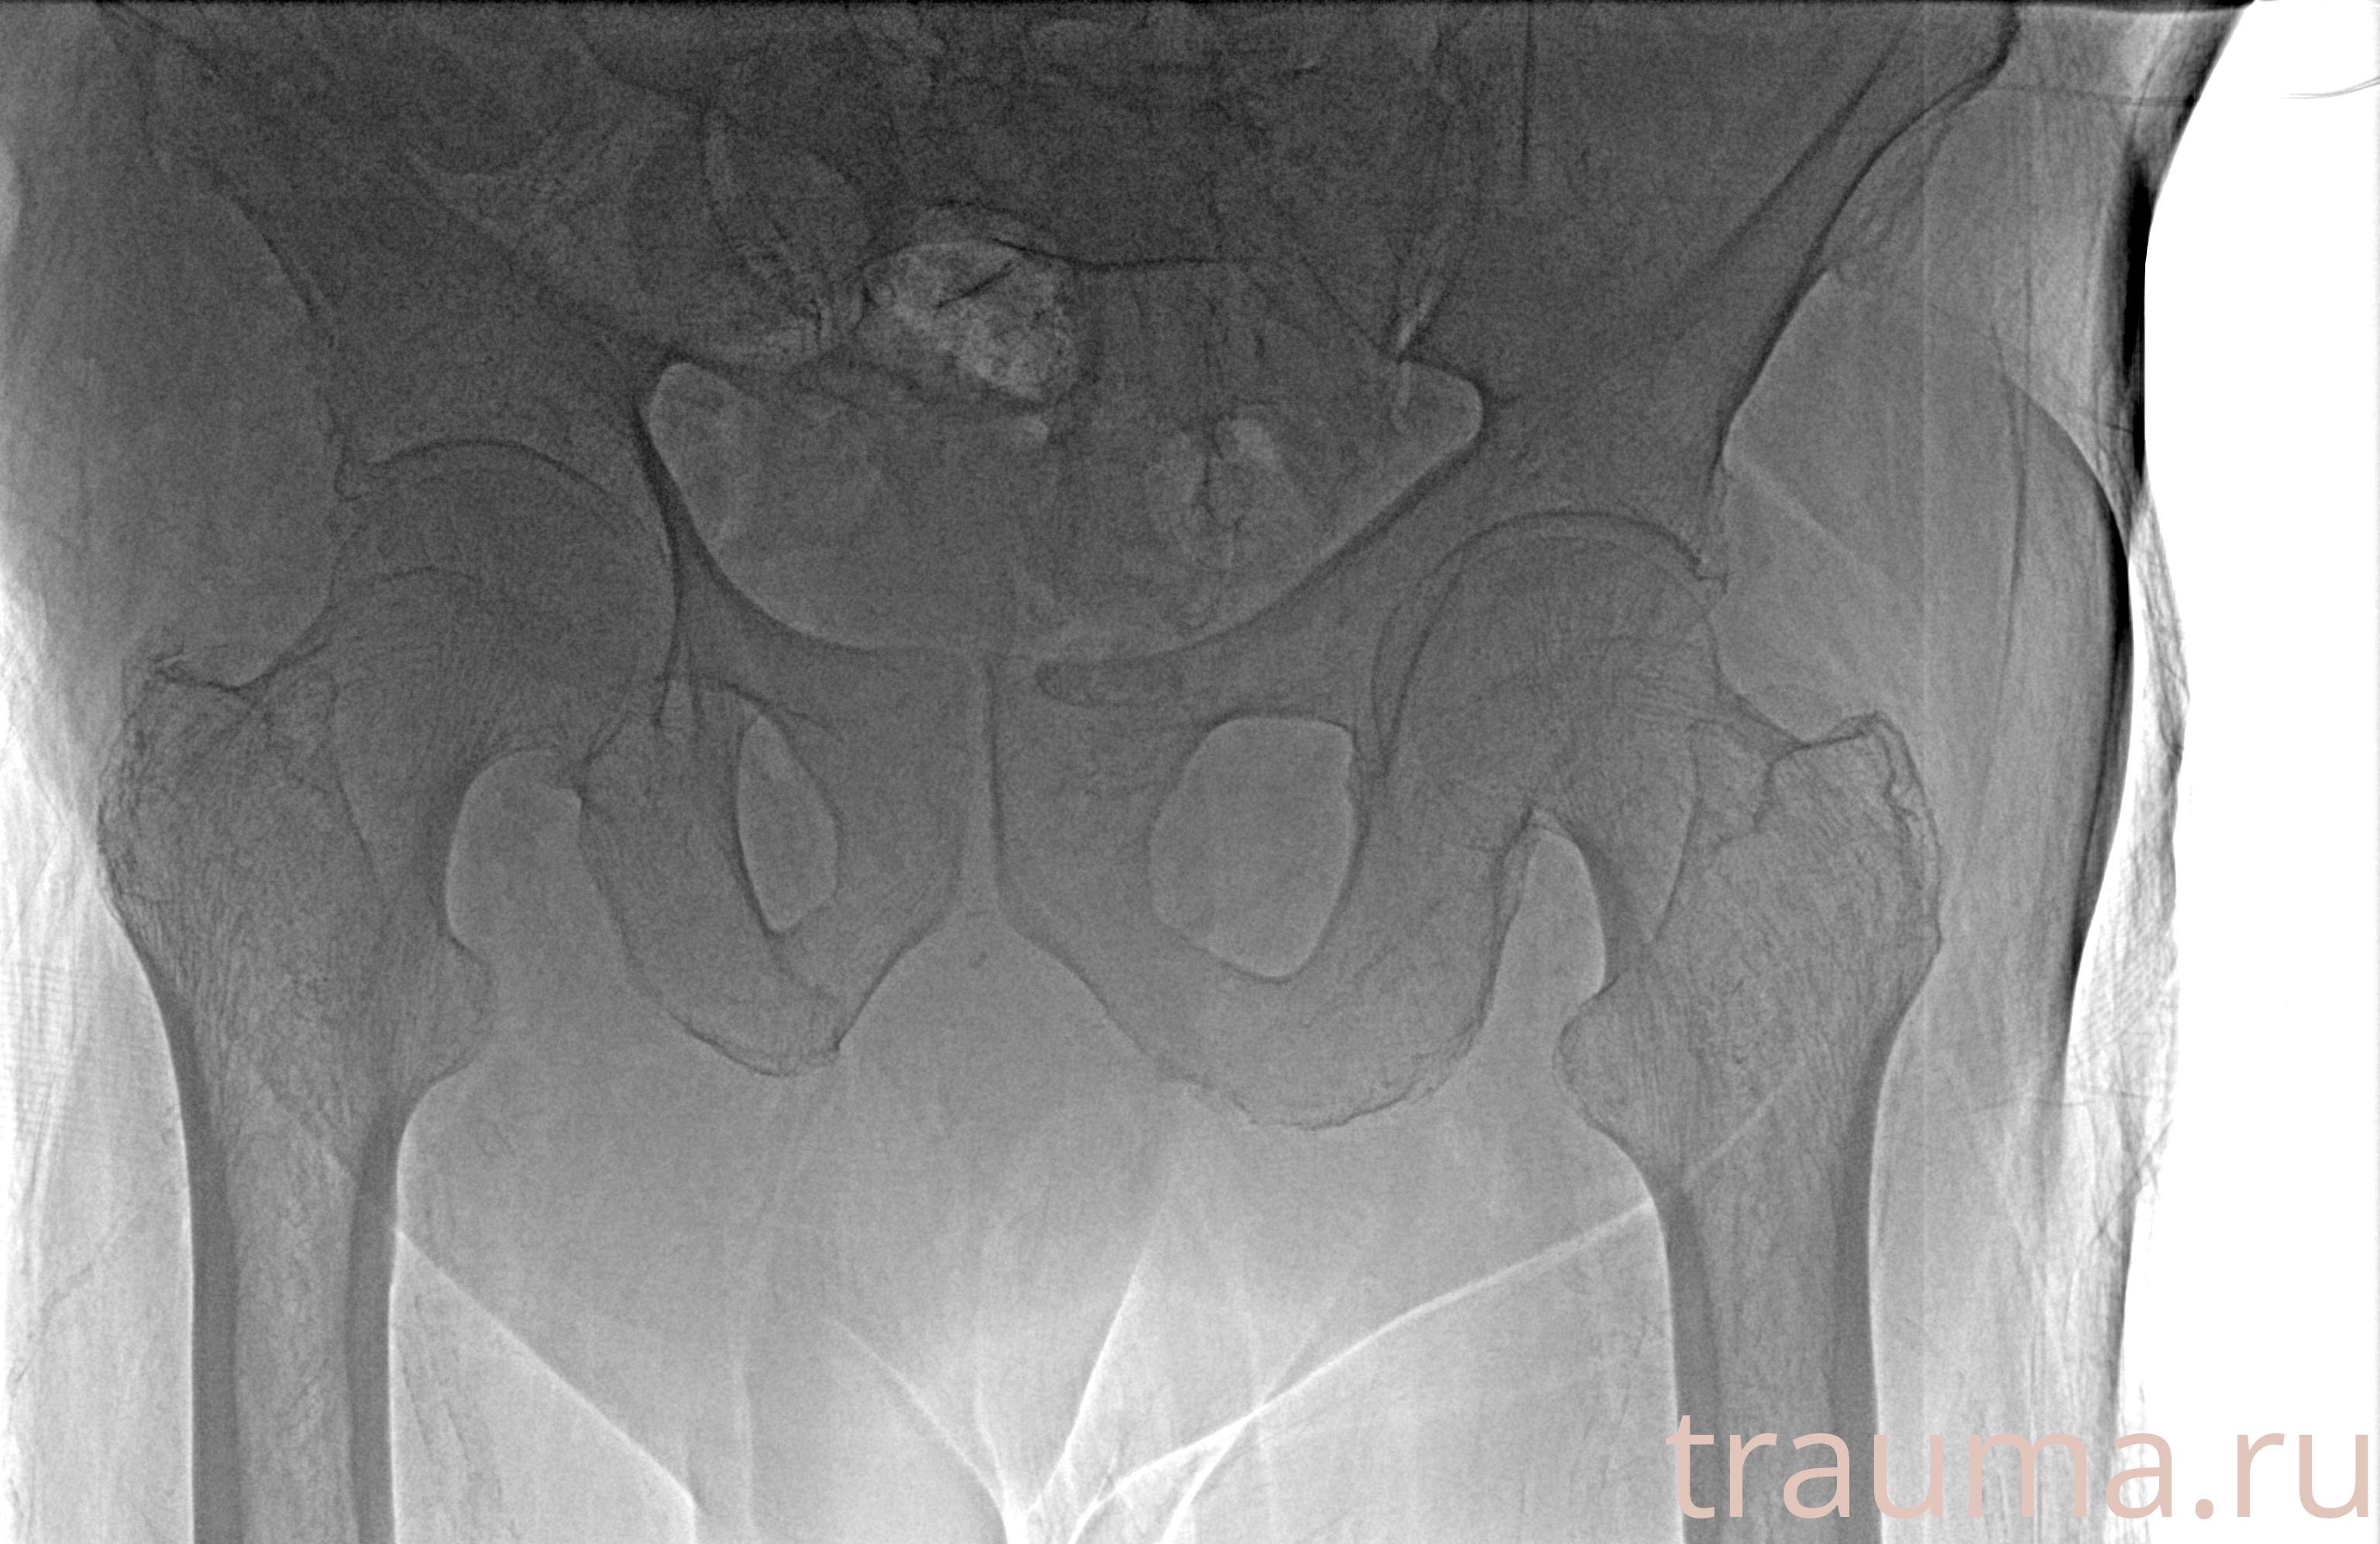

Рентгенограммы

Рентген на дому: по вашему адресу приезжает врач-рентгенолог, травматолог-ортопед с мобильным рентгеновским аппаратом, проводит диагностику травмы или заболевания, делает необходимые рентгенограммы, дает рекомендации по дальнейшему лечению. Получить качественные снимки в домашних условиях возможно благодаря уникальной методике, разработанной МосРентген Центром для института  Склифосовского